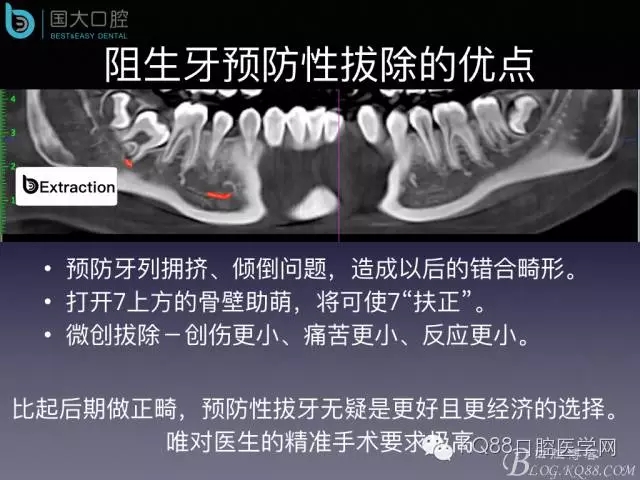

阻生牙的預(yù)防性拔除

- 牙齒拔除適應(yīng)證及第二磨牙遠中齲病